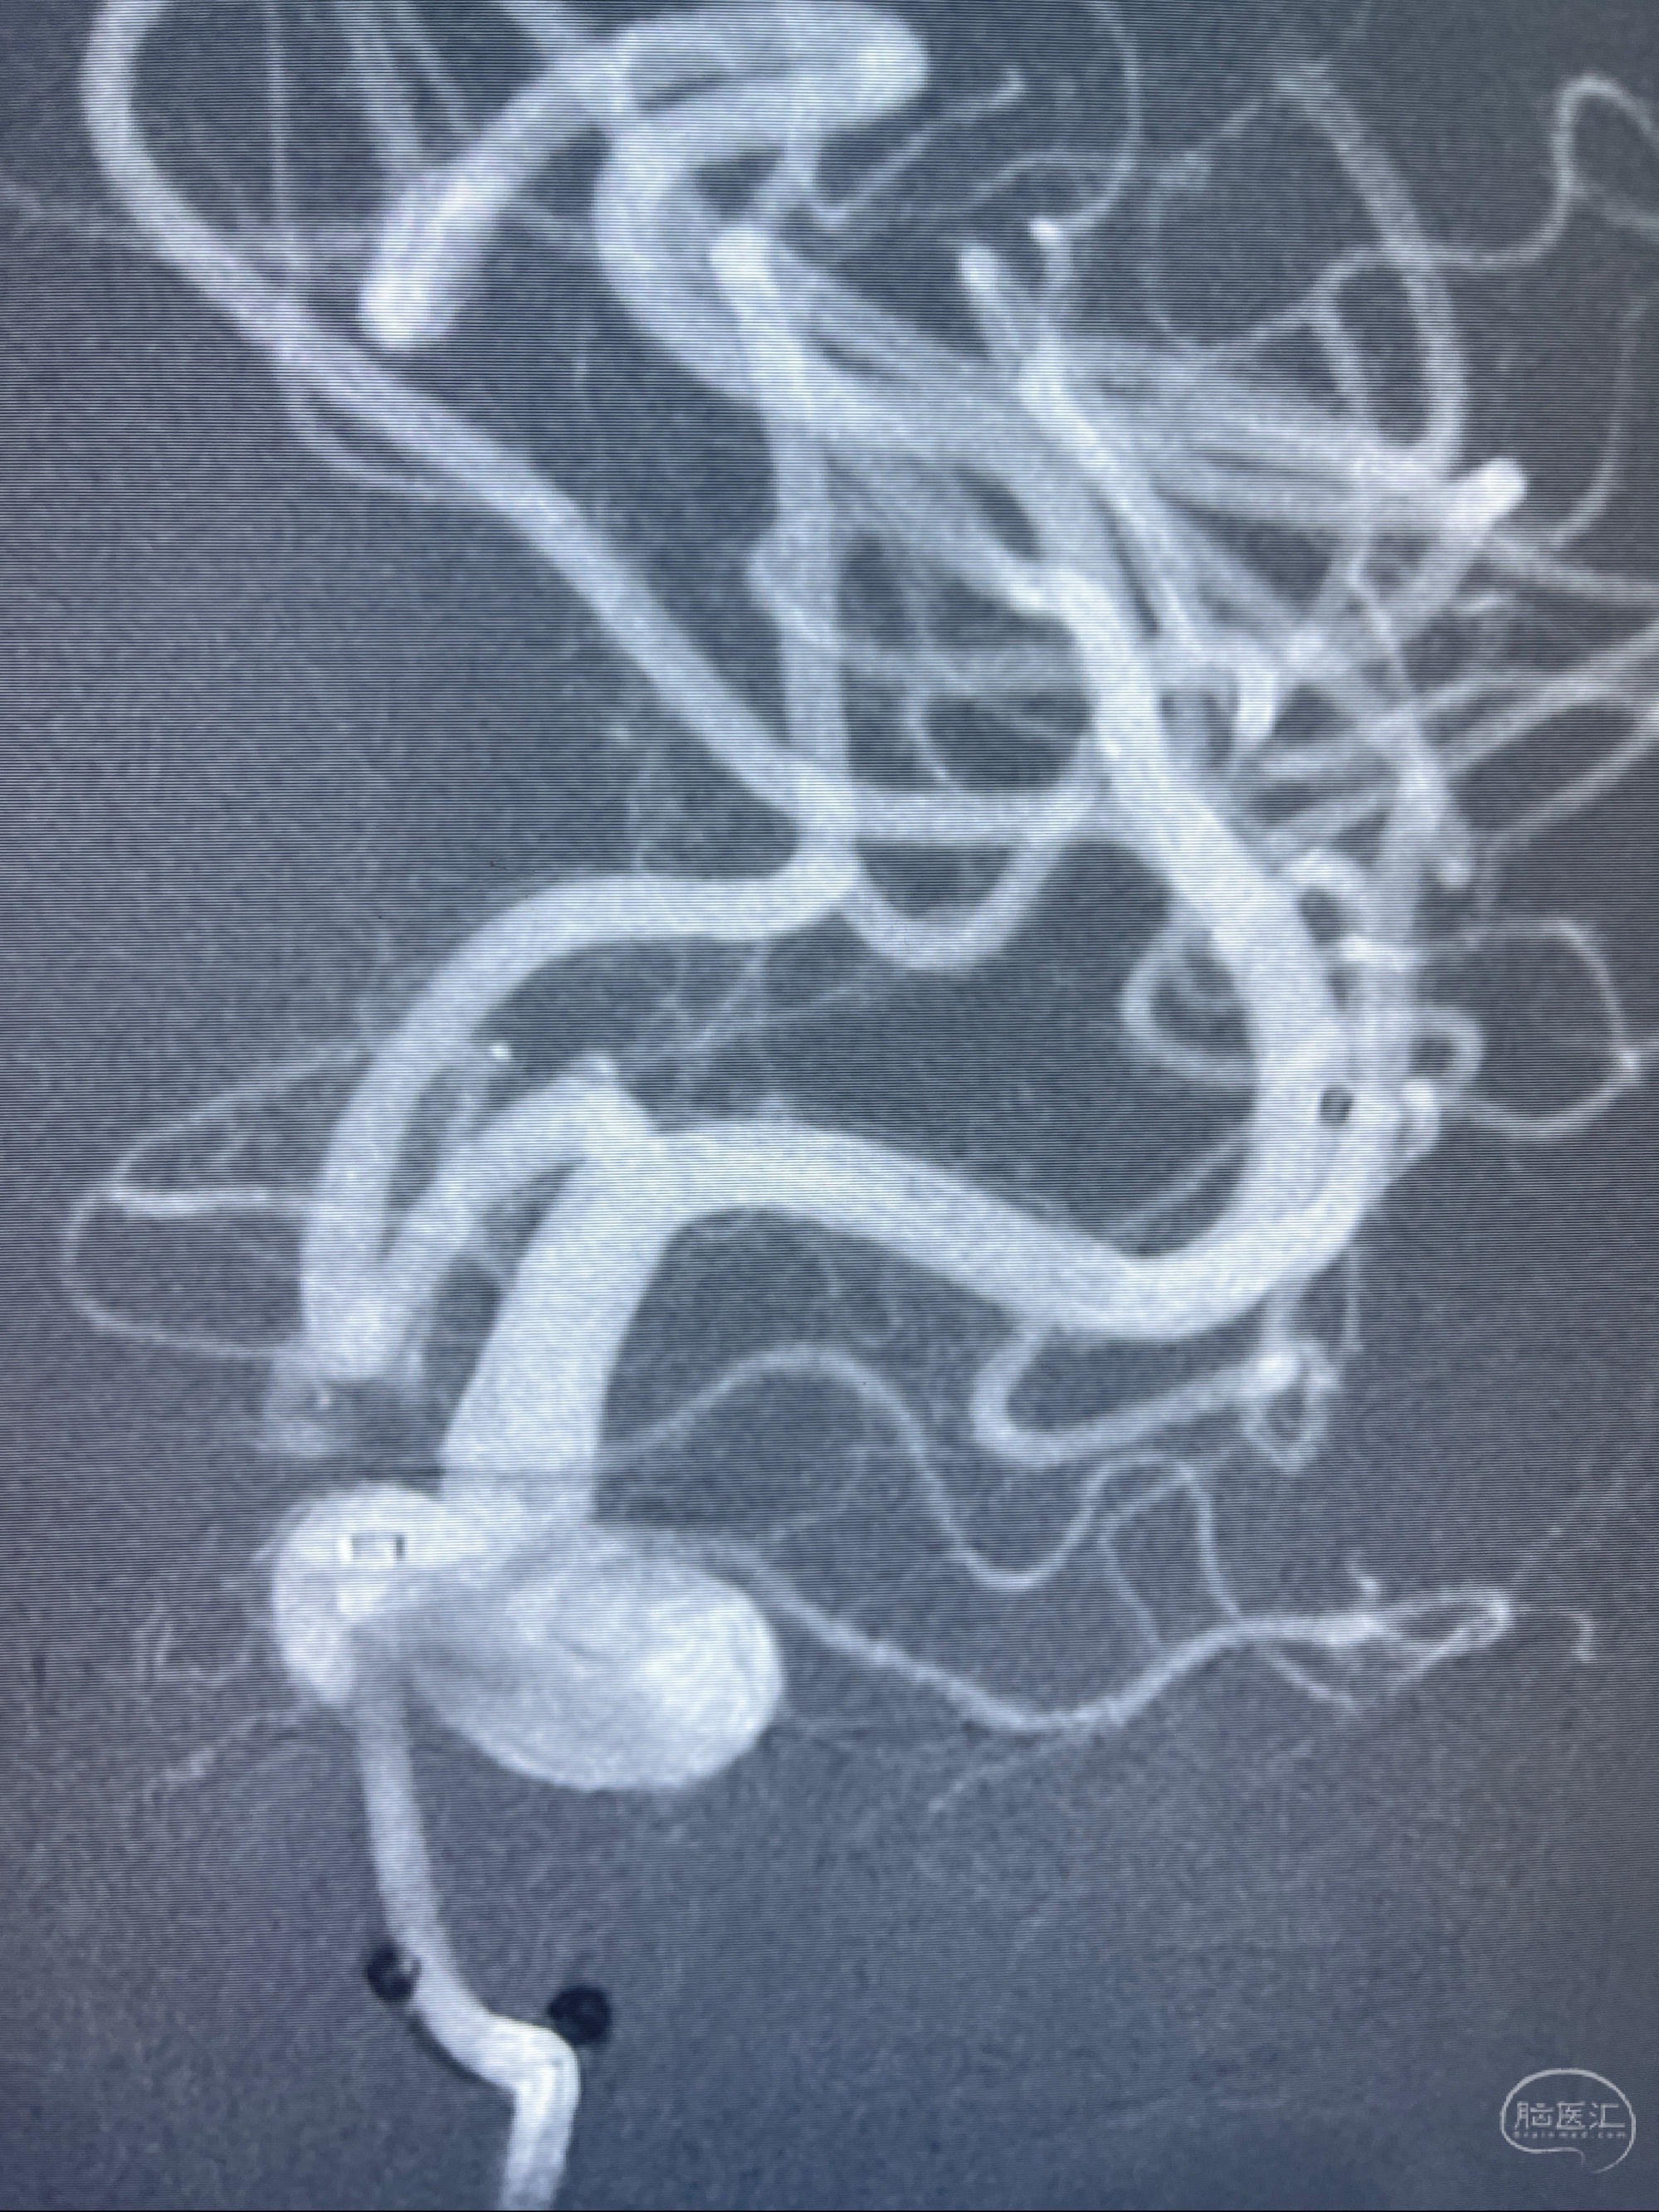

2023-08-01全麻下行双侧颈眼动脉瘤支架辅助栓塞

- pipeling4.5-20mm

- pipeline 4.0-20mm

手术顺利,麻醉苏醒佳,遵嘱动作

术后即刻CT